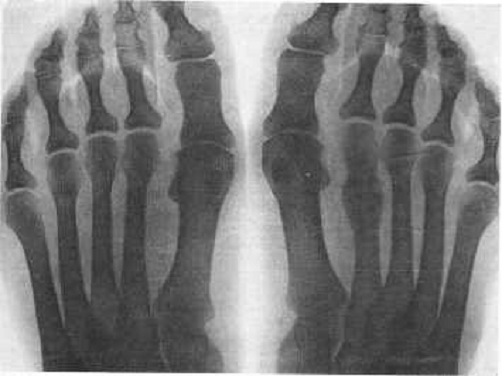

Рентгеновские снимки и их интерпретация